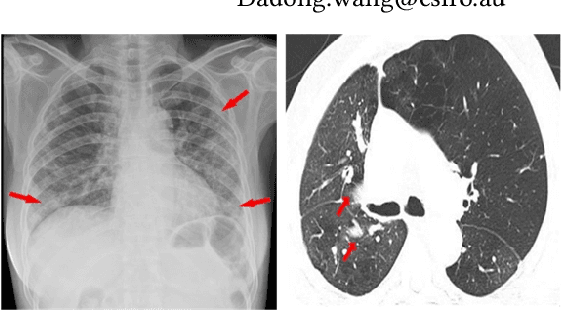

Deep learning technology can be used as an assistive technology to help doctors quickly and accurately identify COVID-19 infections. Recently, Vision Transformer (ViT) has shown great potential towards image classification due to its global receptive field. However, due to the lack of inductive biases inherent to CNNs, the ViT-based structure leads to limited feature richness and difficulty in model training. In this paper, we propose a new structure called Transformer for COVID-19 (COVT) to improve the performance of ViT-based architectures on small COVID-19 datasets. It uses CNN as a feature extractor to effectively extract local structural information, and introduces average pooling to ViT's Multilayer Perception(MLP) module for global information. Experiments show the effectiveness of our method on the two COVID-19 datasets and the ImageNet dataset.